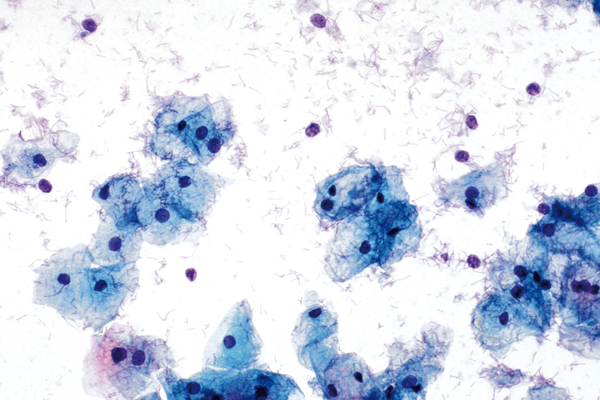

d. Ausreifende Metaplasie (I)

- gleichförmige runde, feingranulierte Zellkerne

- z.T. kleine unauffällige Nucleolen

- zyanophiles Zytoplasma

- normale Kern-Plasma-Relation

- bei reiferen Metaplasien vermehrt Einzelzelllagerung